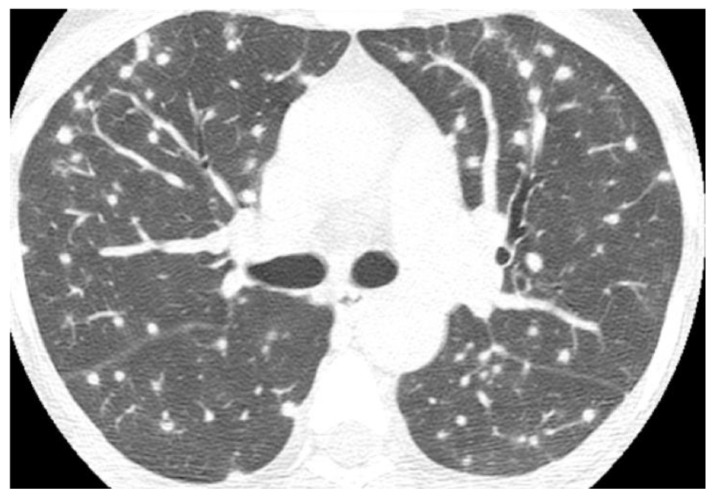

Endemic fungal infections are responsible for high rates of morbidity and mortality in certain regions of the world. The diagnosis and management remain a challenge, and the reason could be explained by the lack of disease awareness, variability of symptoms, and insidious and often overlooked clinical presentation. Imaging findings are nonspecific and frequently misinterpreted as other more common infectious or malignant diseases. Patient demographics and clinical and travel history are important clues that may lead to a proper diagnosis. The purpose of this paper is to review the presentation and differential diagnosis of endemic mycoses based on the most common chest imaging findings.